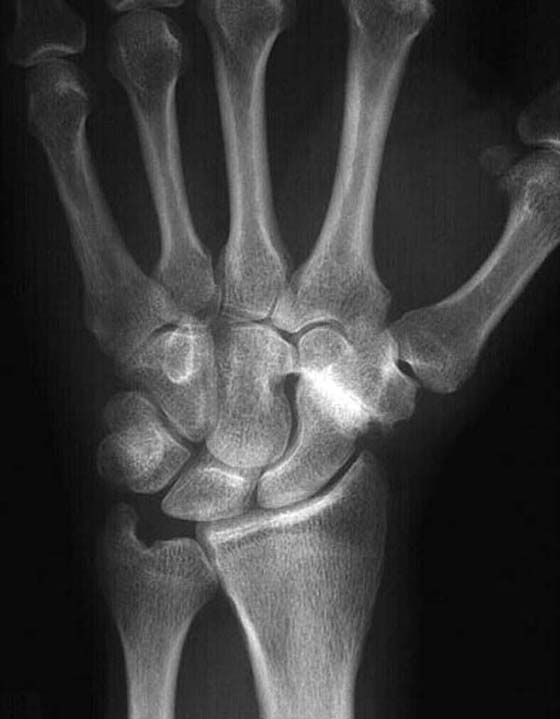

A review of the literature reveals that after four-bone fusion one can expect to see an average flexion–extension arc of approximately 72 to 80 degrees and an average ulnoradial deviation arc ranging from 37 to 53 degrees22,23 (Fig. 76-8, online). Krakauer and colleagues27 report significantly less motion with a 54-degree flexion–extension arc, whereas El Mowafi and colleagues24 report significantly more motion, achieving 75% to 79% of normal contralateral wrist motion.

images

Figure 76-8 A, B, Case study. A 45-year-old right hand dominant (RHD) security officer treated for a scaphoid fracture 10 years earlier presents with a painful wrist. Evaluation demonstrates a scaphoid nonunion advanced collapse deformity. A scaphoid excision with four-corner fusion was performed (see Fig. 76-5). At 4 weeks postoperatively, a thumb spica orthosis was fabricated and gentle wrist active range of motion (AROM) was initiated. At 8 weeks postoperatively, the patient was pain free with normal digital ROM. Wrist AROM was 40 degrees of extension (Fig. 76-8A) and 35 degrees of flexion (Fig. 76-8B), 20/15 degrees of radial/ulnar deviation, and 75/75 degrees of pronation/supination. Grip strength at level III on a Jamar dynamometer was 53 pounds on the right and 70 pounds on the left.